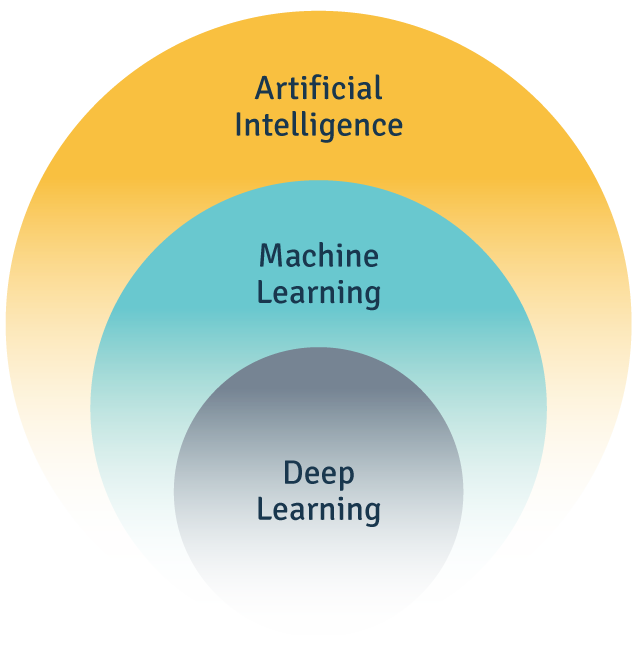

Artificial Intelligence describes the ability of computer programs and machines to mimic human intelligence. It can be further broken down into Machine Learning and Deep Learning.

Machine Learning involves a set of techniques that allow machines to improve at tasks over time. Fujifilm Healthcare's machines get better at predictions as they continue to gather, classify, and examine large amounts of medical images.

Deep Learning is one of the techniques within Machine Learning. It allows the program to use ‘artificial neural networks’ to perform a task repeatedly. The program learns from every cycle and modifies its approach a little each time to produce more accurate results. This technique helps our machines in reconstructing images, enhancing the sharpness of low-resolution scans, and in early detection of cancers.